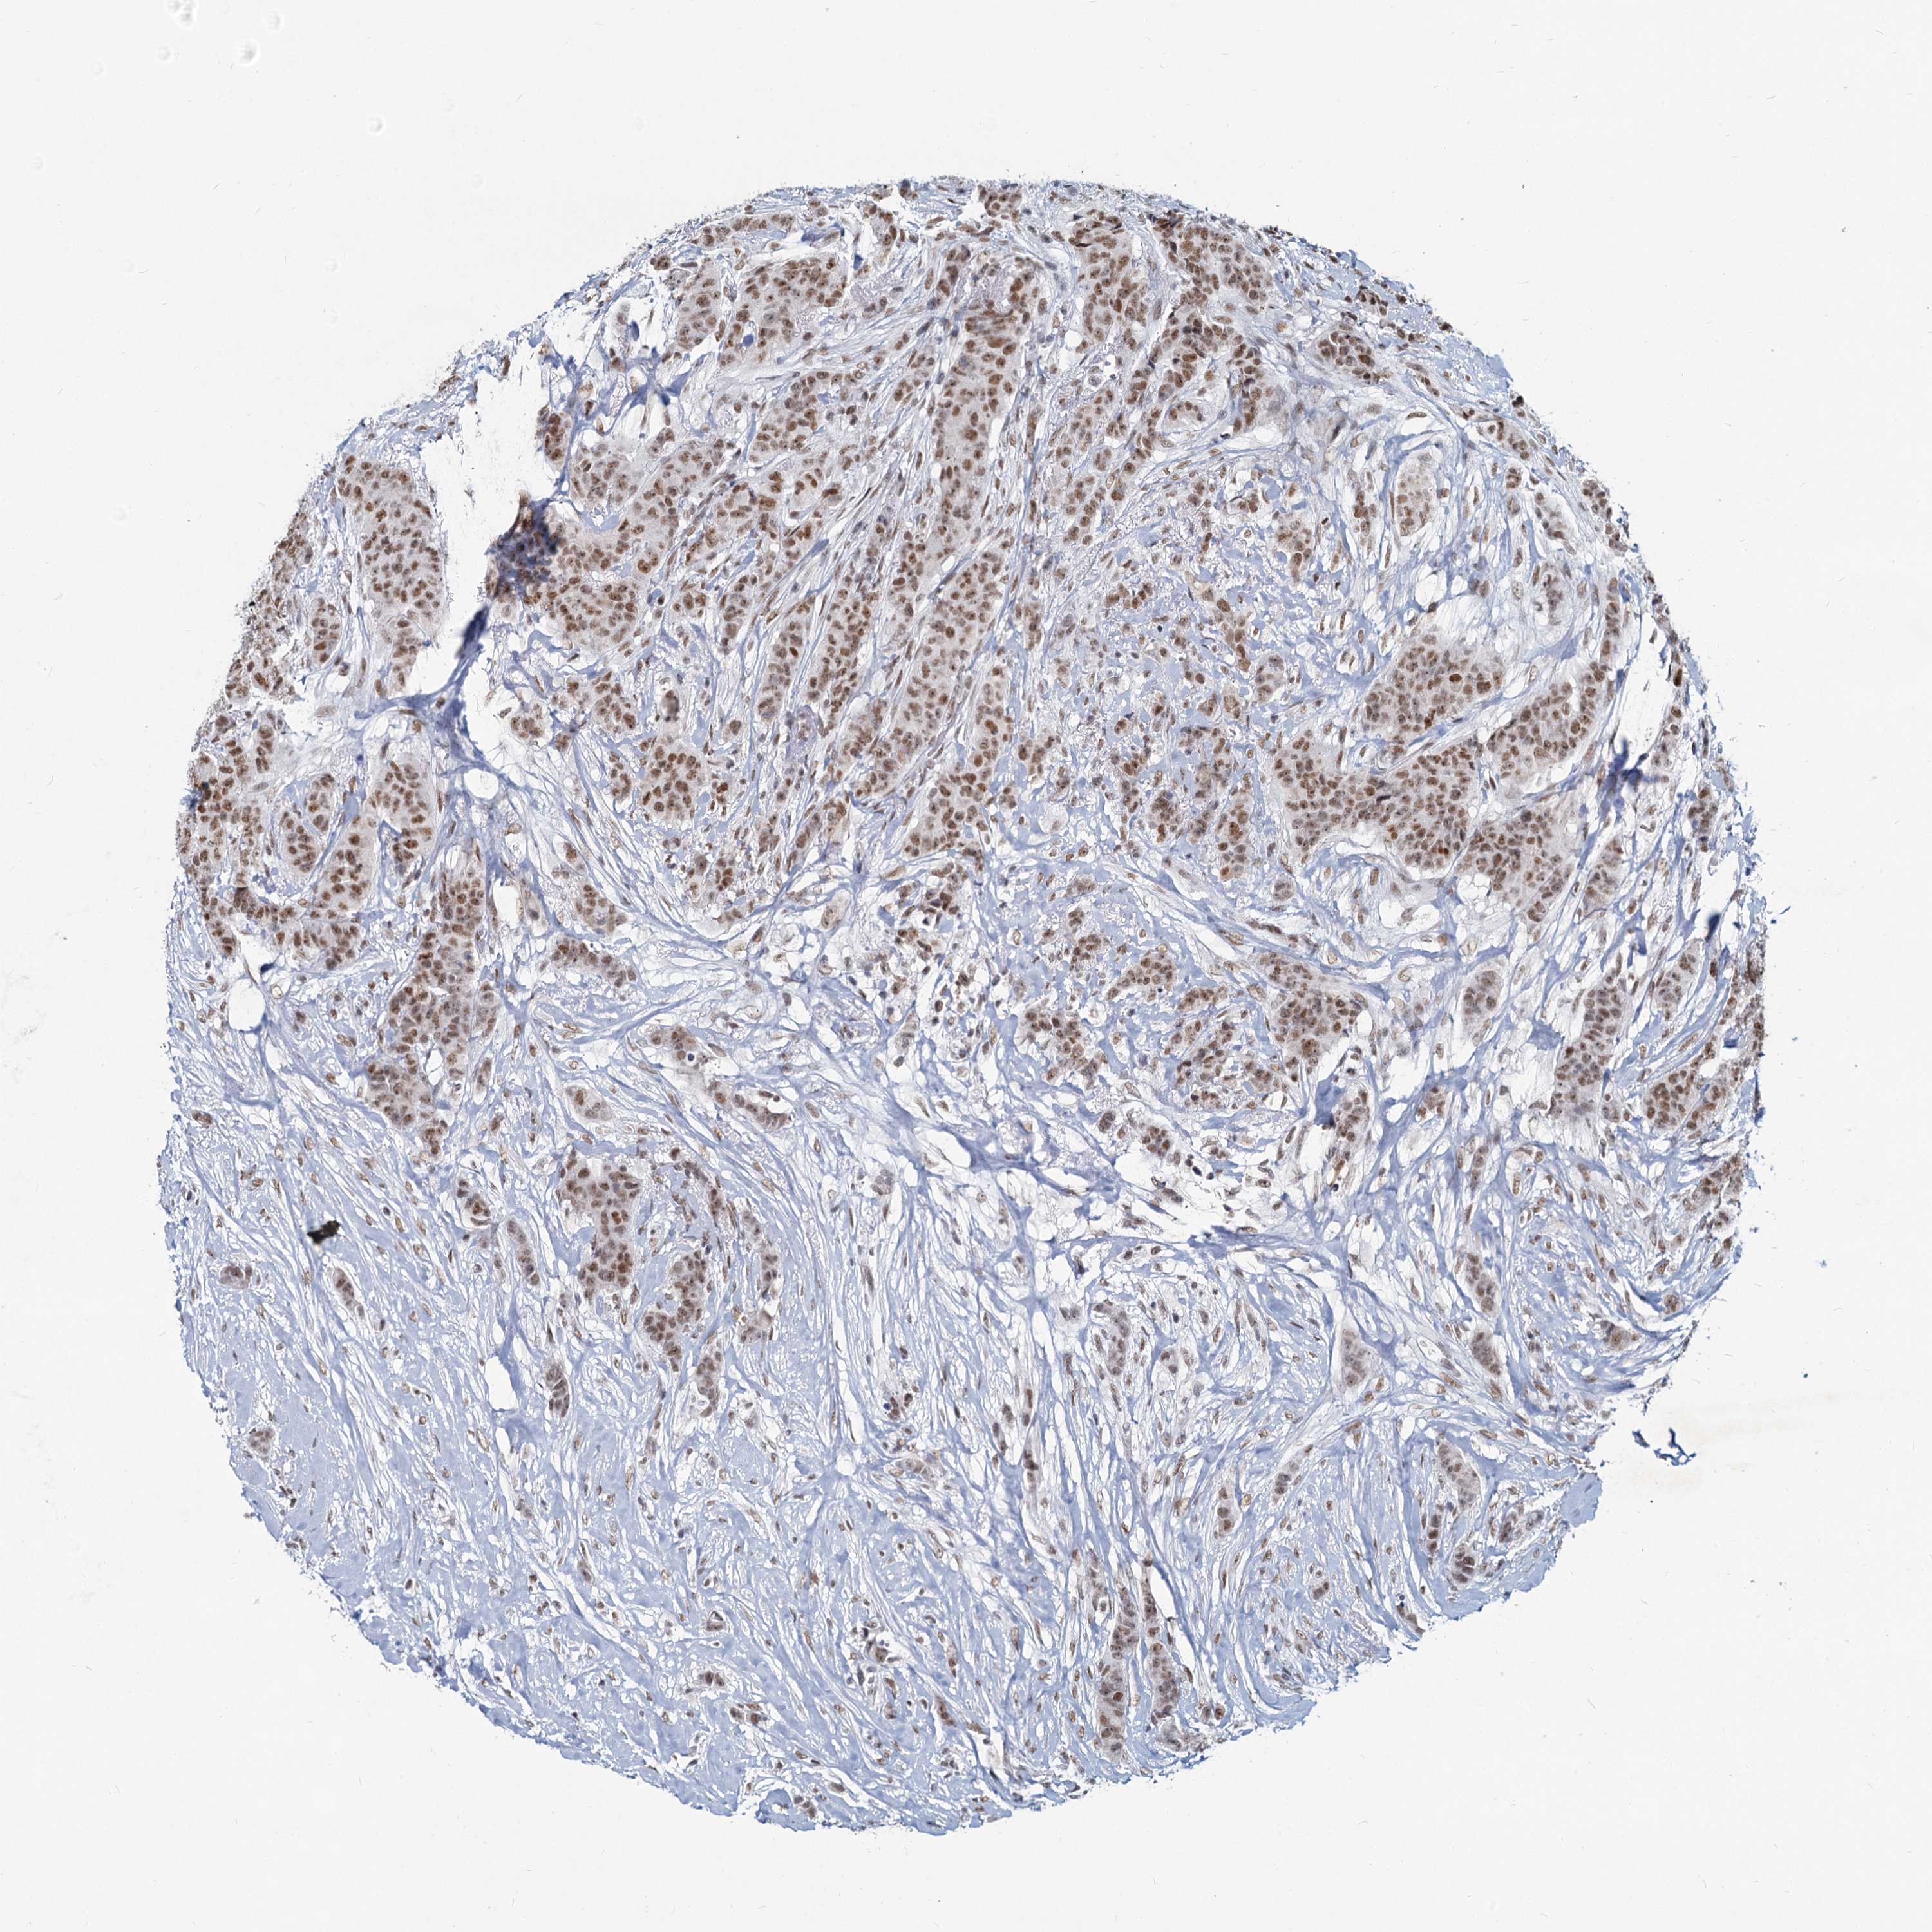

METTL14

CANCER BREAST CANCER Show tissue menu

BRCA TCGA BRCA VALIDATION PROTEIN EXPRESSION

Breast cancer

Human cancer